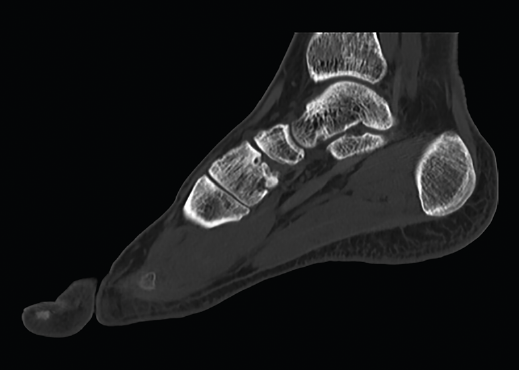

Figura 1. Artrosis primaria de la primera articulación cuneometatarsiana.

Existen distintas opciones de osteosíntesis con tornillos y/o placas. Actualmente, disponemos de diferentes diseños de placas: placas de tipo “Pi” que fijan CMM1-CMM2, placas plantares, mediales, medioplantares o dorsales. Recomendamos el empleo de placas “Pi” si es preciso artrodesar CM-M2 y el uso de placas medioplantares o plantares para la artrodesis aislada de CM-M1, que desde el punto de vista biomecánico son más apropiadas (Figuras 1 a 3). Otro tema de debate es el empleo de injerto óseo esponjoso autólogo o de sustitutivos óseos como la matriz ósea desmineralizada o trifosfatos cálcicos. Recomendamos, especialmente en pacientes menores de 50 años, el empleo de injerto autólogo de cresta ilíaca.